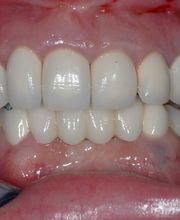

Das Bodensee Implantat Zentrum (ZIP) ist Ihre führende Praxis für Zahnheilkunde in der Region. Wir sind spezialisiert auf hochwertige Implantologie, einschliesslich des All-on-4® Konzepts, für das wir als Excellence Center Gold-zertifiziert sind. Unser Leistungsspektrum umfasst Komplettsanierungen, Kronen, Brücken sowie ästhetische Behandlungen. Mit über 30 Jahren Erfahrung bieten wir auch Angstpatienten eine einfühlsame Betreuung und Behandlungen unter Narkose für ein strahlendes Lächeln.